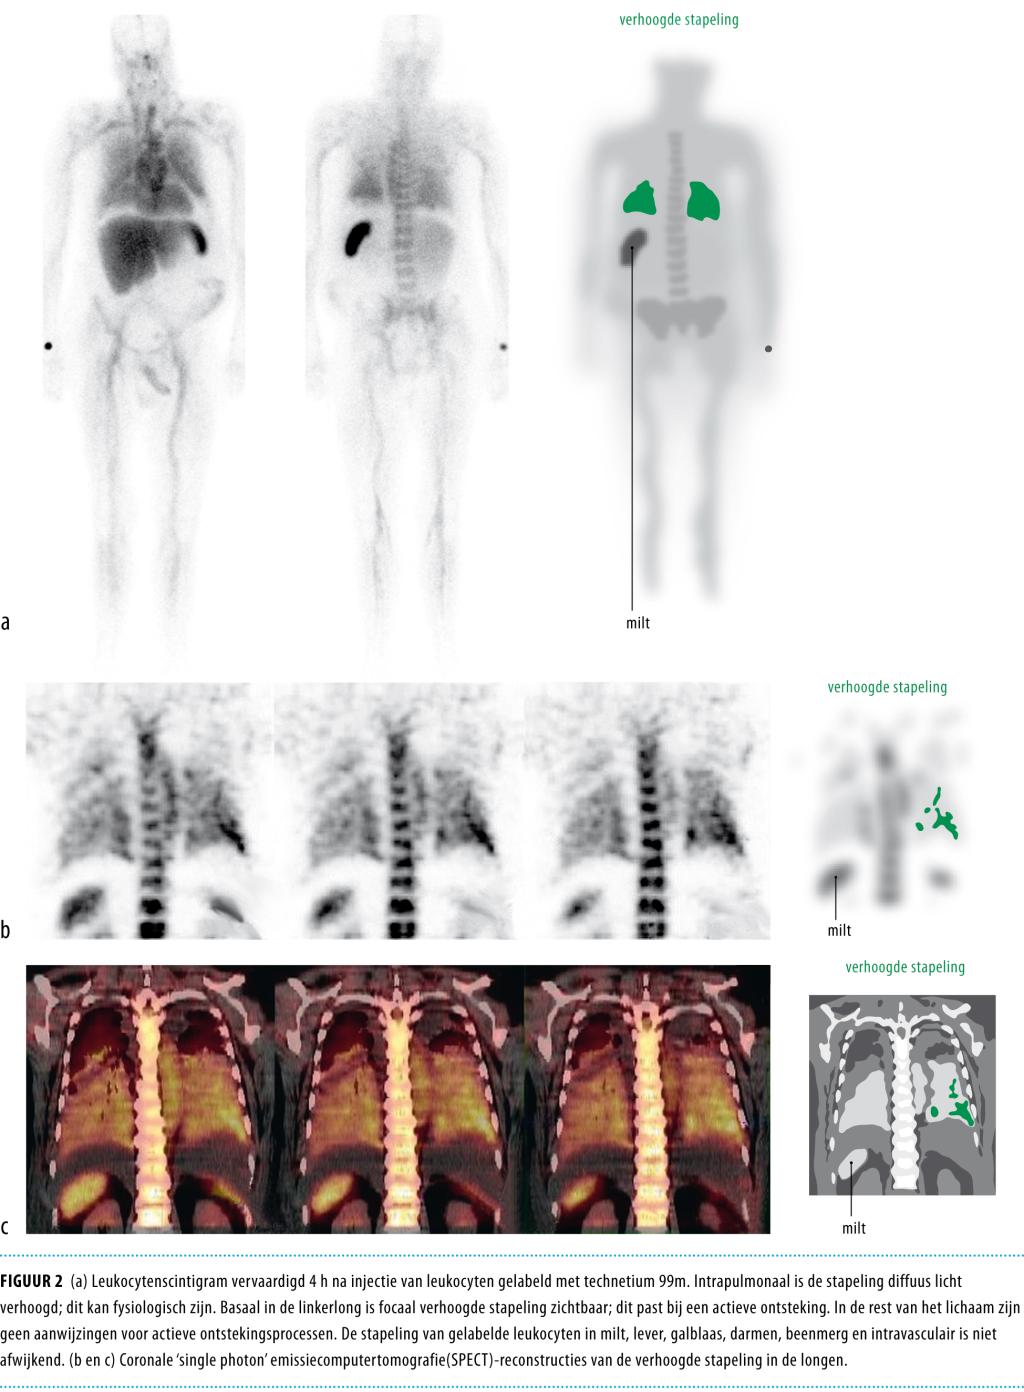

Een 62-jarige man met fors alcoholgebruik in de voorgeschiedenis, presenteerde zich met atypische neurologische verschijnselen. De diagnose ‘bacteriële meningitis’, veroorzaakt door Streptococcus pneumoniae, werd een dag later gesteld. Ondanks antibiotische behandeling ontstond het beeld van decompensatio cordis en multi-orgaanfalen. Hij had tevens een endocarditis met insufficiënte mitralis- en aortakleppen. Later waren er ook aanwijzingen voor een pulmonale locatie van de infectie. Omdat de ontstane hemodynamische situatie onhoudbaar was, werd besloten tot dubbele hartklepvervanging, ondanks het extreem hoge operatierisico en de extracardiale infectiehaarden die met leukocytenscintigrafie werden aangetoond. Patiënt overleed postoperatief. De combinatie van meningitis, pneumonie en endocarditis op basis van de S. pneumoniae wordt het syndroom van Austrian genoemd. Dit syndroom komt zelden voor en heeft vaak een ernstig beloop. Het houdt sterk verband met asplenie, functionele asplenie of hyposplenie, zoals dat voorkomt bij alcoholabusus. Vroege herkenning en een combinatie van antibiotische en chirurgische behandeling is essentieel.